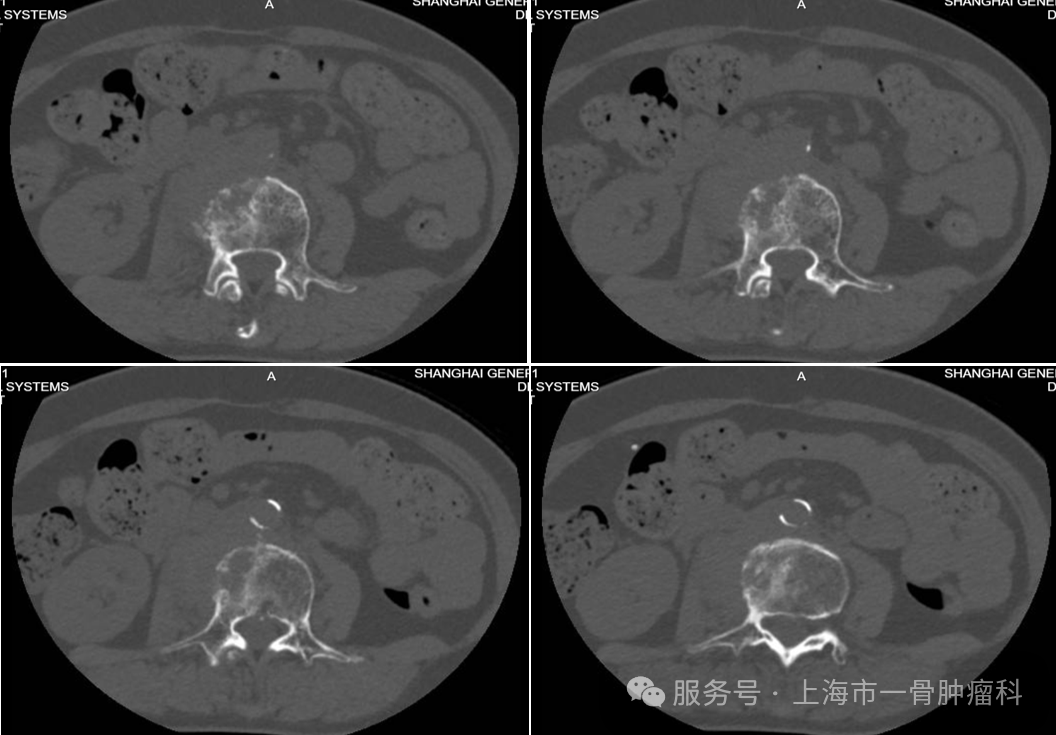

图2:术前腰椎CT:L3椎体混合型骨质破坏伴椎旁受累